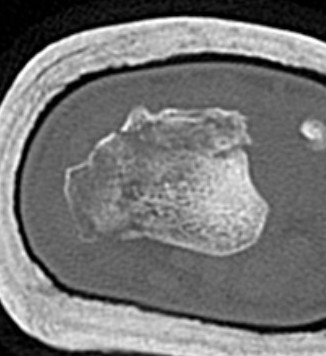

CT

Radial styloid + dorsal rim fractures